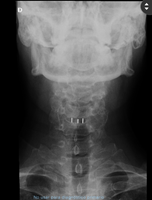

En C5-C6 cambios degenerativos con complejo disco osteofitario que condiciona estenosis moderada del canal raquídeo cervical, apreciando signos de mielopatía compresiva. Estenosis foraminal bilateral moderada en C5-C6 e izquierda leve en C6-C7 |

Se aprecia la prótesis de disco colocada entre C5 y C6 | ||||